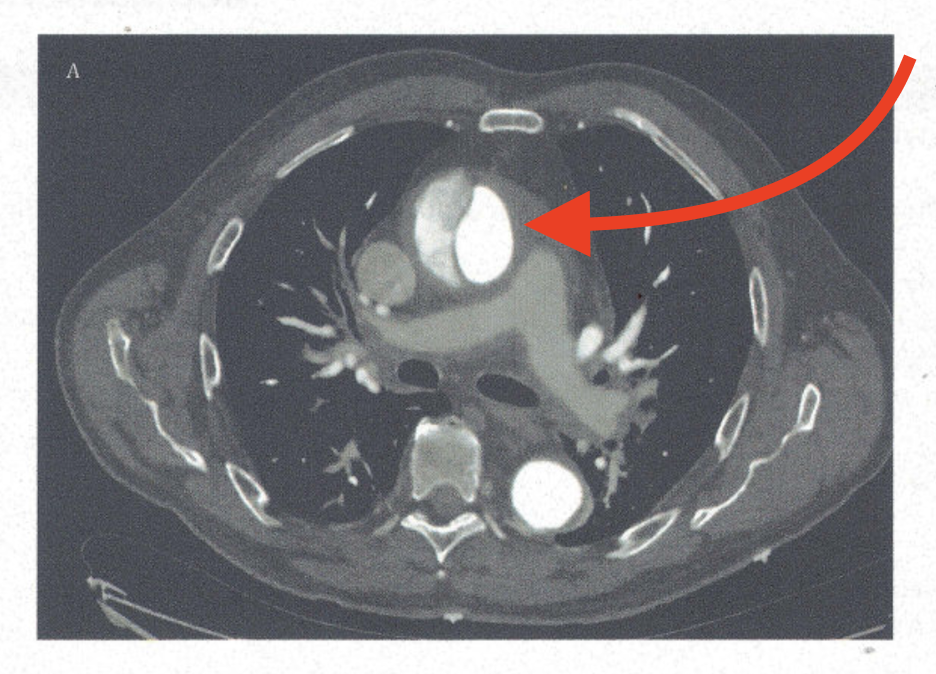

What is the test of choice for diagnosing aortic dissection in hemodynamically stable patients?

CT angiography (CTA).